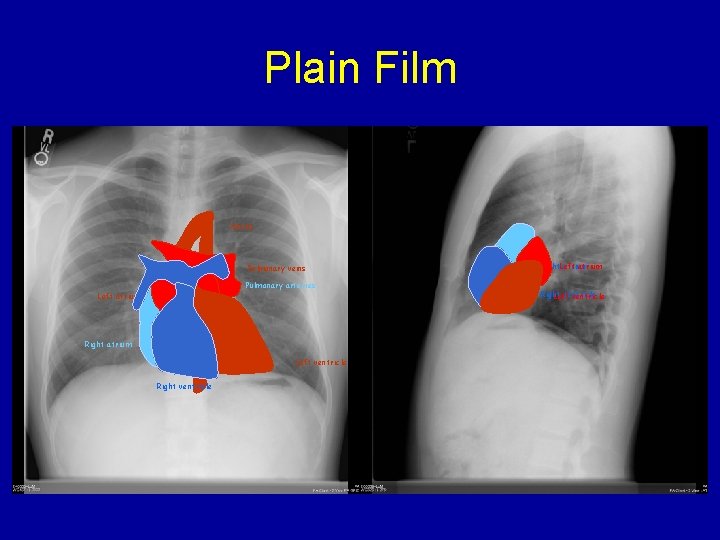

Plain Film Aorta Pulmonary veins Pulmonary arteries Left atrium Right atrium Left ventricle Right. Left atrium Right ventricle Left ventricle